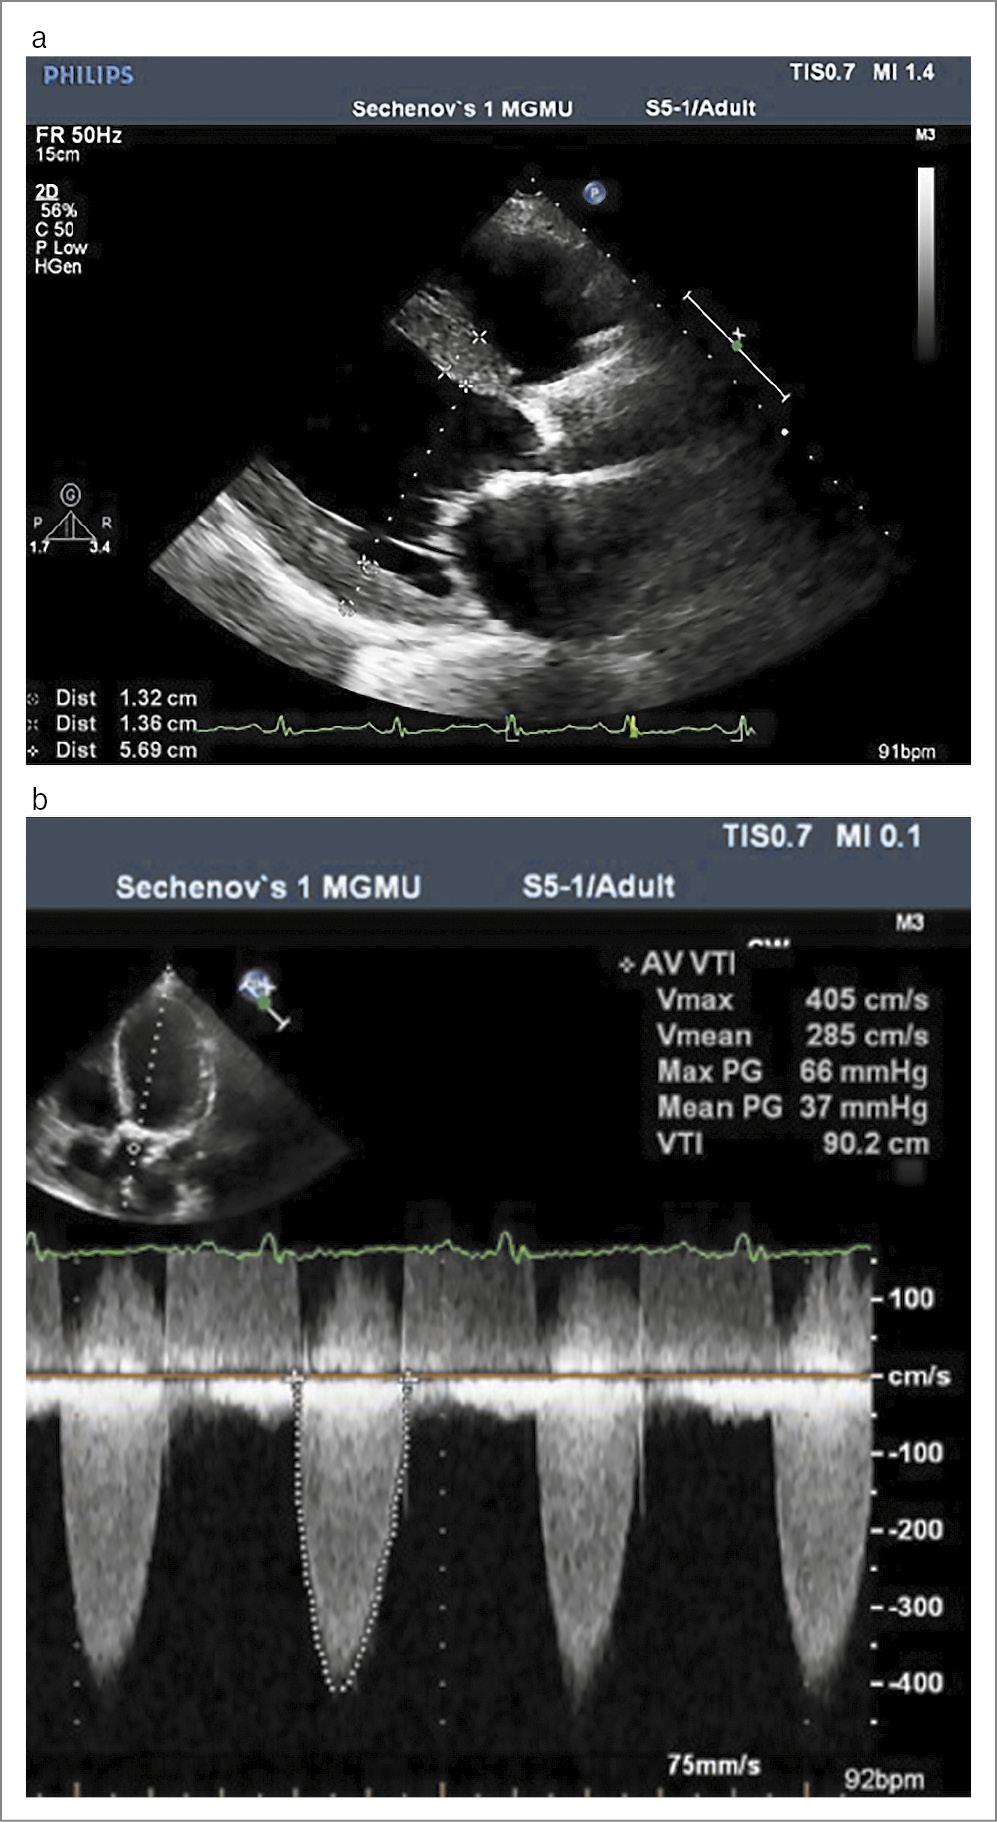

ЭхоКГ: левое и правое предсердия увеличены. ЛЖ: конечный диастолический размер – 5,7 см (норма – до 5,6 см), толщина межжелудочковой перегородки – 1,35 см, толщина задней стенки ЛЖ – 1,3 см (норма – до 1,1 см), конечный диастолический объем – 163 мл, конечный систолический объем – 123 мл. ФВ – 23%. Правый желудочек: переднезадний размер – 3,6 см. Аортальный клапан: створки кальцинированы, амплитуда раскрытия снижена, регургитация 2-й степени. Максимальный градиент давления – 66 мм рт. ст., средний градиент – 37 мм рт. ст. Максимальная скорость кровотока – 405 см/с. Площадь аортального клапана – 0,5–0,6 см2. Митральный клапан: створки умеренно кальцинированы, подвижность створок не ограничена. Регургитация 1–2-й степени. Трикуспидальный клапан: подвижность створок не ограничена, регургитация до 2-й степени. Нижняя полая вена не расширена, на вдохе спадается менее чем на 50%. Заключение: кальциноз аортального клапана с формированием его критического стеноза. Диффузный гипокинез миокарда. Митральная регургитация от умеренной до средней. Аортальная регургитация до средней степени. Легочная гипертензия (систолическое давление в легочной артерии – 50 мм рт. ст.); рис. 1.

Рис. 1. ЭхоКГ пациентки З.: a – утолщение створок аортального клапана и фиброзного кольца. Умеренная гипертрофия ЛЖ; b – допплерЭхоКГ демонстрирует тяжесть аортального стеноза: максимальная скорость кровотока – 405 см/с, средний градиент – 37 мм рт. ст. (недооценивается в условиях низкой сократительной функции).